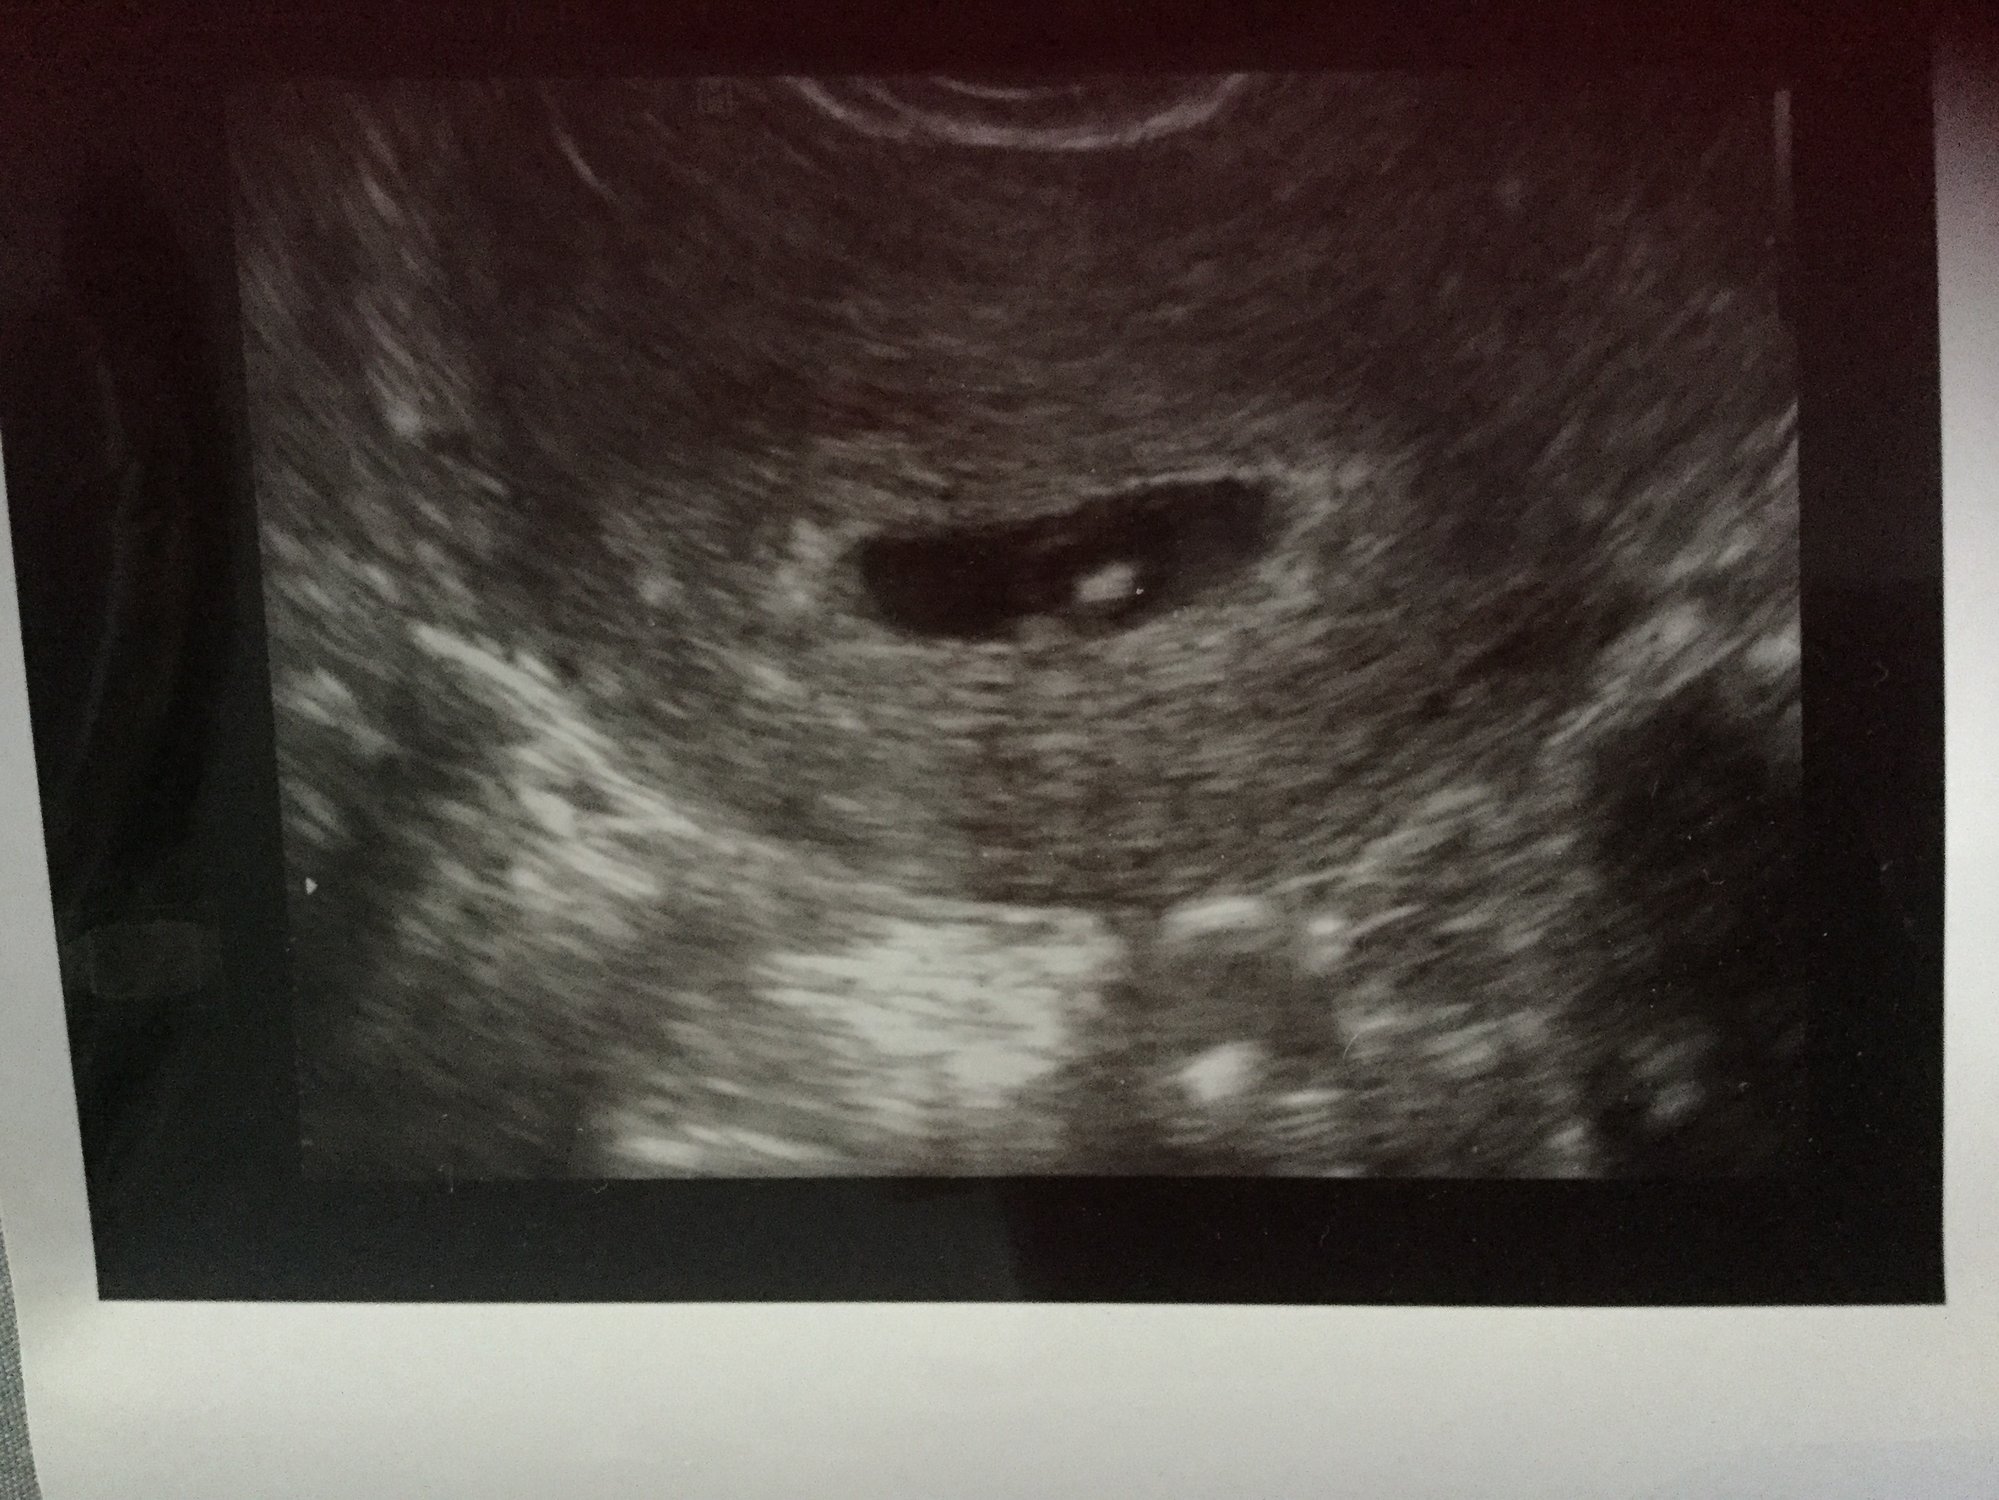

Hi ladies! Something fun for this Sunday afternoon. I've been seeing a lot on Pinterest the ramzi theory. Early on in sonograms earlier than 10 weeks you can tell the sex of the baby by which side the placenta is on. Placenta on the right= Boy left = girl any of you ladies use this before. I can't tell from my picture at all. Remember you need to know if your sonogram is flipped regardless of transvaginal or tummy.

I would say the thickest part would be on the left, but find it very hard to locate. But if it is left, it's s girl according to Ramzi theory.

Maybe this weeks us will show better, mine did at 8 weeks in my eyes.